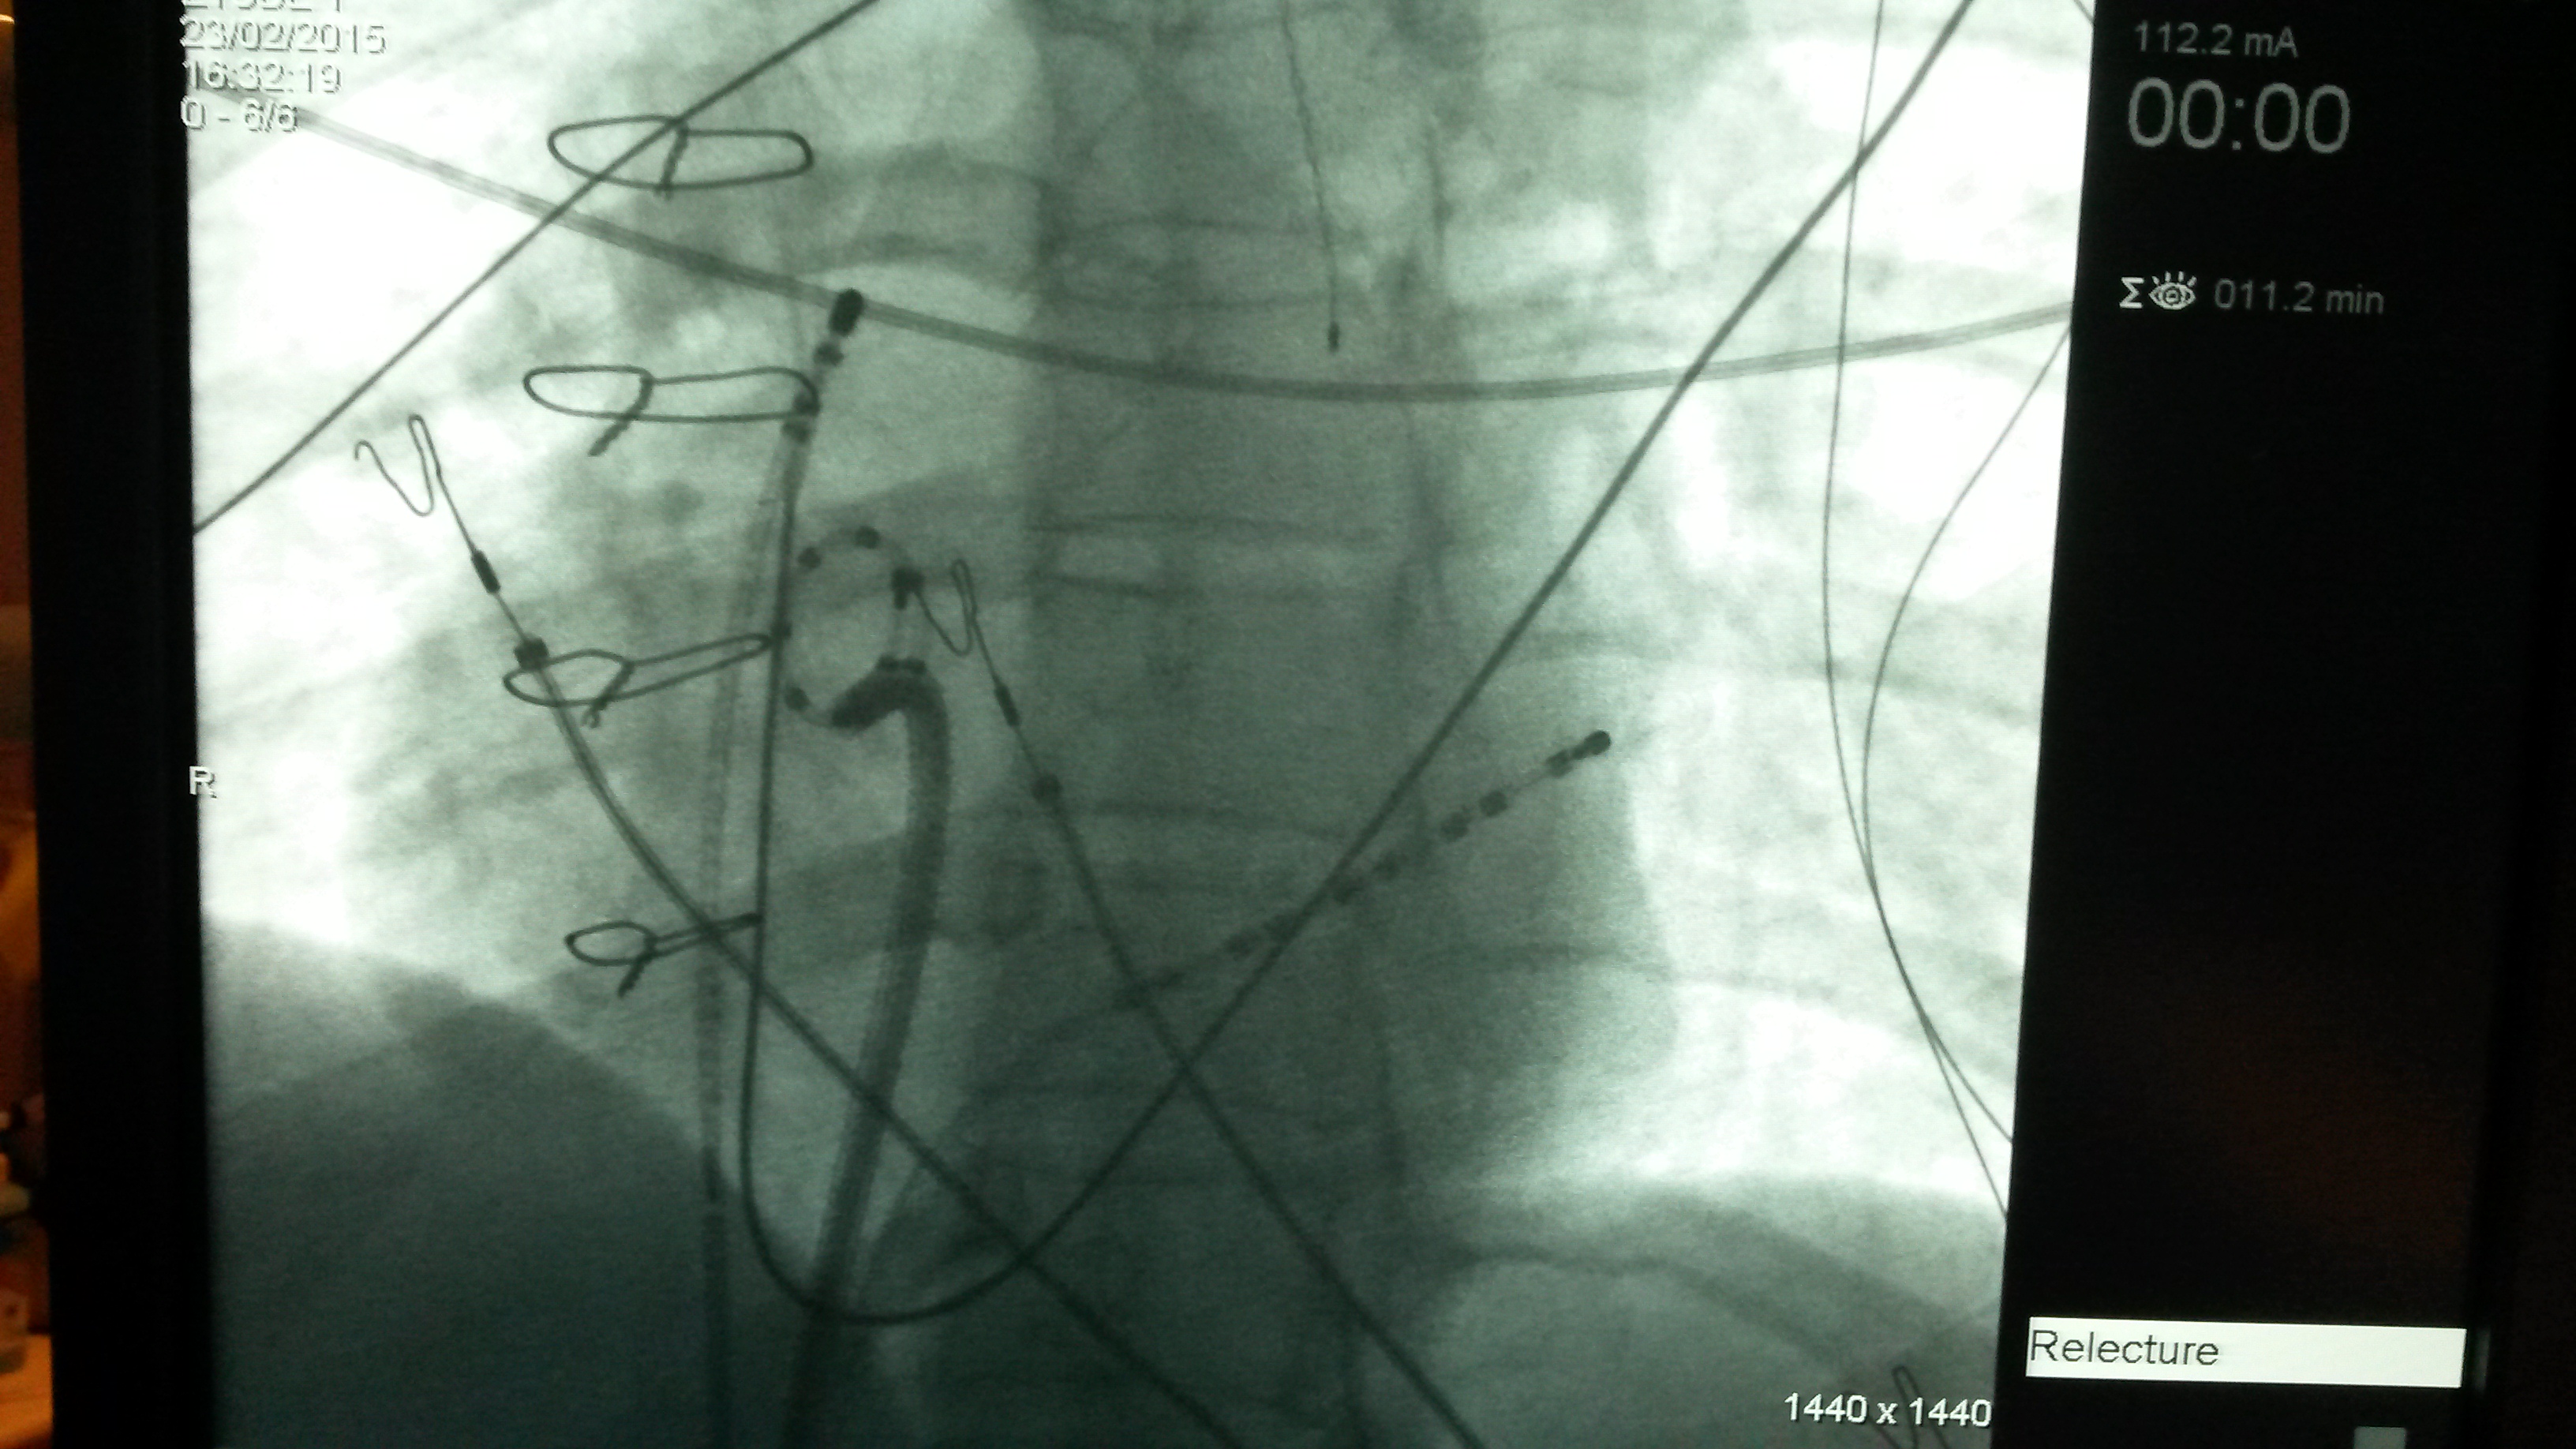

Vue per-opératoire par radioscopie de l'ombre cardiaque avec les cathéters positionnés à l'intérieur: sonde décapolaire dans le sinus coronaire, lasso dans la veine pulmonaire inférieure droite via la gaine transseptale, sonde d'ARF à l'ostium de la veine cave supérieure. A noter des fils d'acier de fermeture de sternotomie chez cette patiente ayant été opérée du coeur qqs années auparavant. (Dr Poindron) Séquence ETO (Echocardiographie TransOesophagienne) lors d'une ponction transseptale : vérification de la vacuité de l'auricule gauche, visualisation du septum inter-auriculaire (SIA), purge de la gaine avec épreuve de contraste, mise en tension du SIA avec le système gaine-dilatateur-aiguille puis traversée du SIA

(images Dr D. Poindron).